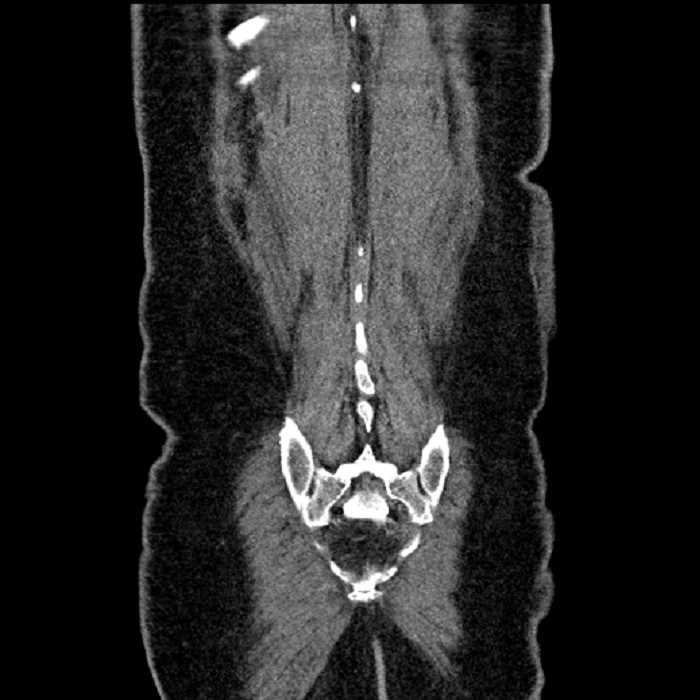

Age: 63

Sex: Male

Indication: Abdominal pain

• Ankylosis of both sacroiliac joints

Acute sigmoid diverticulitis complicated by a small contained perforation and a large abscess in the right hepatic lobe. Additional small subcapsular abscesses along the anterior margin of the left hepatic lobe.

Additionally, loss of the normal fat plane between the peridiverticular collection and adjacent thickened loops of small bowel raises the potential for an enterocolonic fistula.

Hepatic abscess showing the double target sign with low density internally surrounded by a thin inner enhancing rim (red arrow) and ill-defined outer low density rim (yellow arrow). Blue arrow indicates an internal septation. Red arrows: additional smaller subcapsular abscesses. Red arrow: focal contained perforation associated with diverticulitis.